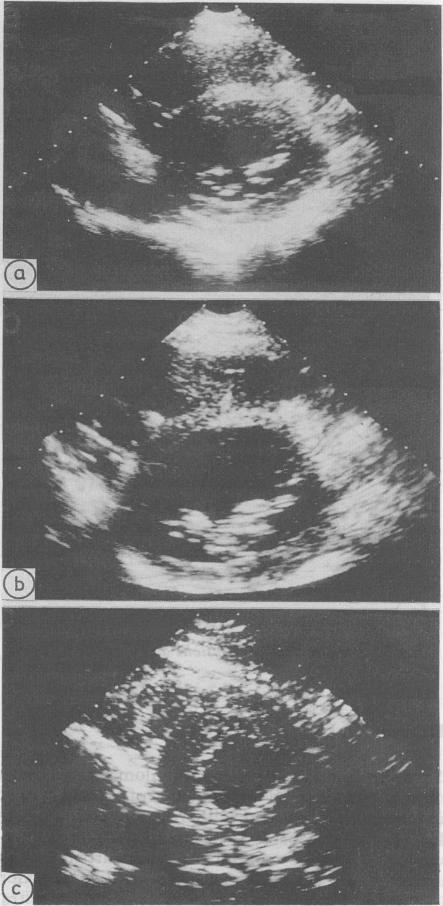

The diagnosis of cardiac sarcoidosis, particularly when there is no overt systemic involvement, is frequently delayed because of its varied manifestations. Focal left ventricular wall motion abnormalities were recognised in five patients with sarcoidosis. Three patients showed abnormal regional wall motion in the basal portion of the ventricular septum and free wall with sparing of the apex. The angiographic appearances supported the echocardiographic findings which were atypical of ischaemic heart disease. The remaining two patients both had diffuse left ventricular hypokinesia, with a focal abnormality that was most pronounced in the anteroapical region; this pattern is often seen with coronary disease. The recognition by echocardiography or angiography of focal abnormalities of wall motion affecting the basal portion of the ventricular septum should suggest the possibility of myocardial sarcoidosis even in the absence of recognised systemic manifestations.

心脏结节病的诊断常常会延迟,尤其是在没有明显全身受累的情况下,因为其表现多样。在5例结节病患者中发现了局灶性左心室壁运动异常。3例患者在室间隔基部和游离壁出现异常节段性壁运动,心尖未受累。血管造影表现支持了超声心动图的结果,这些表现并非缺血性心脏病的典型表现。其余2例患者均有弥漫性左心室运动减弱,伴有在前壁心尖区最为明显的局灶性异常;这种模式常见于冠心病。即使在没有公认的全身表现的情况下,超声心动图或血管造影发现影响室间隔基部的壁运动局灶性异常也应提示心肌结节病的可能性。